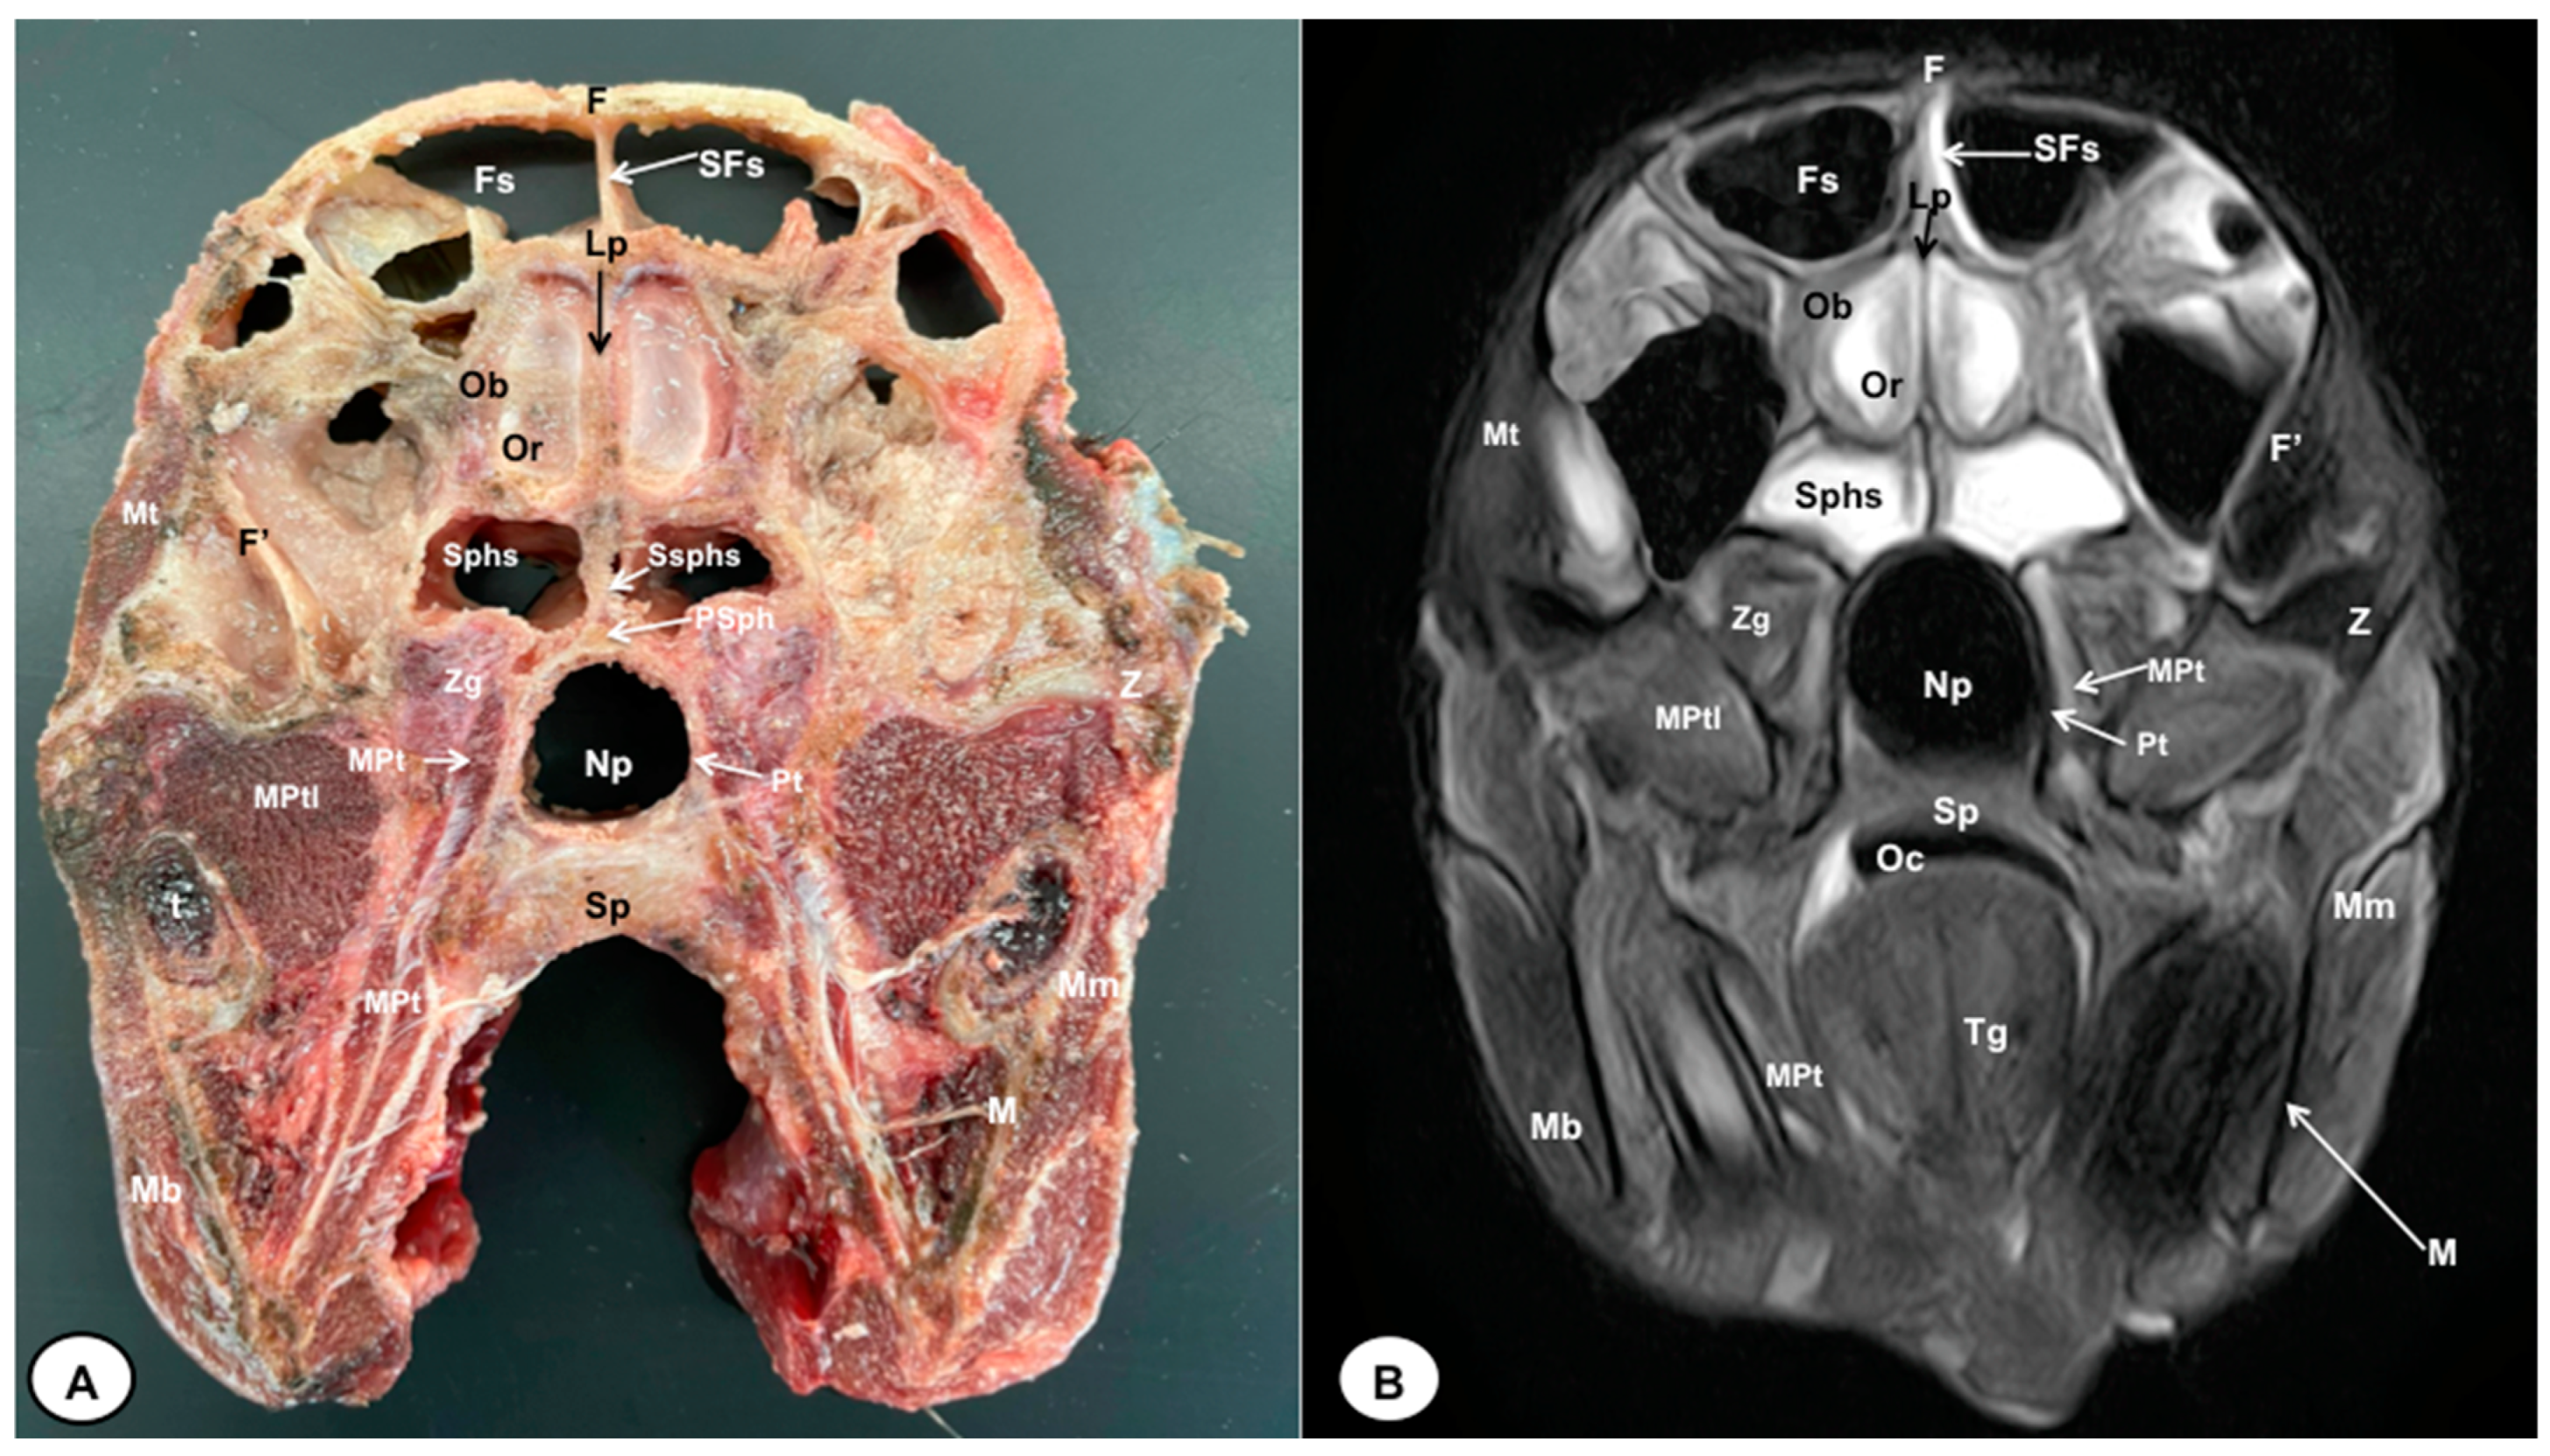

3.1. Anatomical Cross-Sections

3.2. Magnetic Resonance Imaging (MRI)